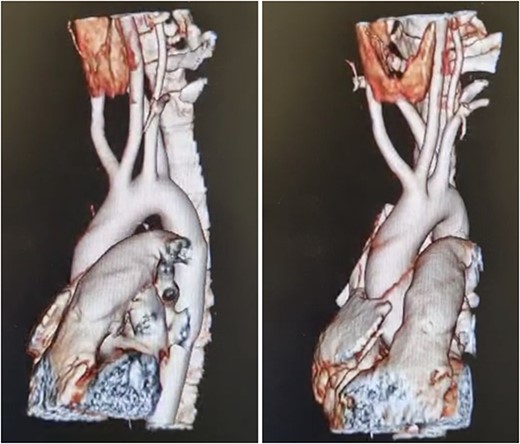

Patient is an 18-year-old female without past medical history. She suffered a 2-month gradually progressive dysphagia accompanied by mild reflux. At first, it was treated as gastroesophageal reflux disease (GERD), and proton pump inhibitors were given with poor results. Dysphagia became so severe at one point that she could not drink any liquid, including saliva; therefore, she presented at our hospital. Clinical examination, including palpation of her peripheral pulses, was unremarkable; therefore, additional exams were required. An esophagogram (Fig. 1) revealed an extrinsic compression above the level of the aortic arch. With these findings, a computed tomography angiography was requested and demonstrated aberrant anatomy of the aortic arch; the carotid arteries arise from one common trunk, the truncus bicaroticus, and an ARSA was found compressing the esophagus as it crossed behind it. There was no evidence of Kommerell’s diverticulum, aneurysmal dilation, or other abnormalities (Fig. 2A and B).

(A) CT, showing and ARSA compressing the esophagus, (B) CT, truncus bicaroticus and an ARSA.